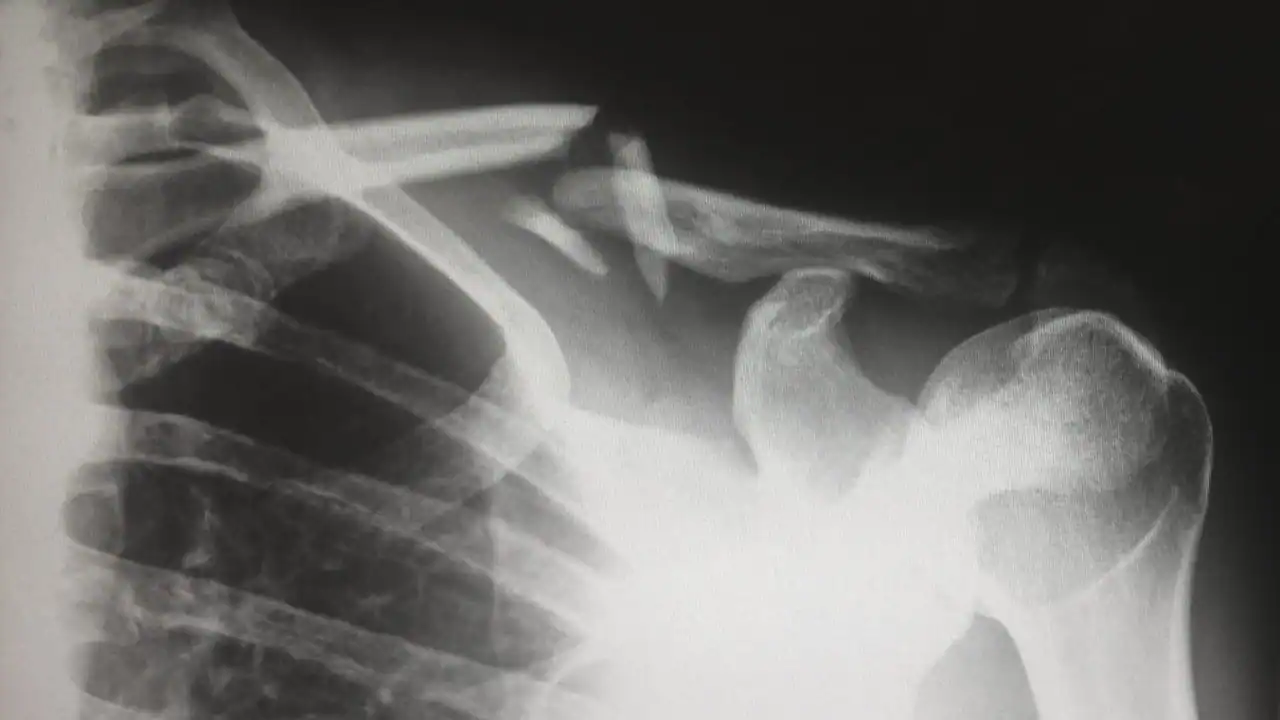

Intelligenza Artificiale Prosegue l’assalto dell’intelligenza artificiale ai radiologi Con l’affinarsi delle capacità delle intelligenze artificiali, i radiologi potrebbero presto restare senza…Jackie Snow22/01/2018

Business I robot chirurghi rubano ai giovani medici le opportunità per imparare il mestiere Fino a pochi anni fa, gli apprendisti potevano apprendere il mestiere direttamente dai…Erin Winick21/01/2018